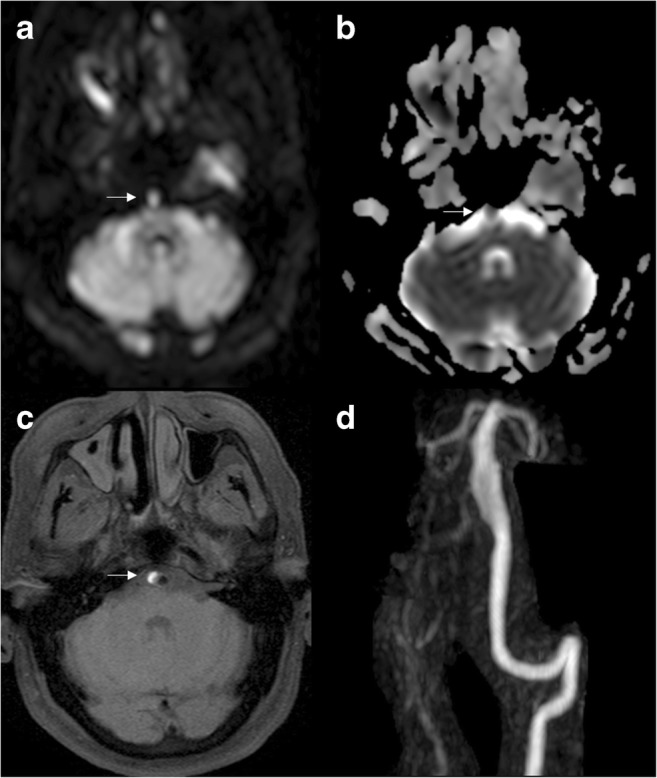

Fig. 3.

Arterial dissection. DWI (a), ADC (b), non-contrast FAT SAT T1 (c) and coronal MIP reconstruction of the basilar artery (d) demonstrate a dissection with mural haematoma represented by the “crescent sign” (arrows), which shows restricted diffusion and hyperintensity on T1WI